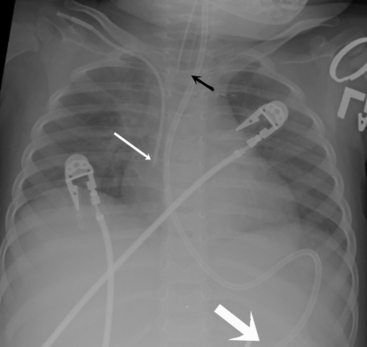

The aortic knob and the trachea will be displaced if a mediastinal shift occurs. When significant atelectasis is present, the trachea and aortic knob usually are displaced toward the area of collapse, because of the volume loss associated with the atelectais.22 However, if a large pleural effusion or pneumothorax is present, the trachea and aortic knob typically will be displaced away from the involved lung and toward the unaffected side, because these problems represent volume gain in the chest (Fig. 10-10).

image

Fig. 10-10 Tension pneumothorax. This 5   month old with complex congenital heart disease was noted by the nurse to have respiratory distress, including tachypnea and nasal flaring. The nurse also noted decreased breath sounds and chest expansion in the left chest and tracheal deviation to the right. This supine anteroposterior film was obtained and demonstrated a left-sided tension pneumothorax (white arrows). The trachea (black arrow) and aortic knob are displaced away from the involved left hemithorax and toward the unaffected right side because of the increased volume associated with the pneumothorax.